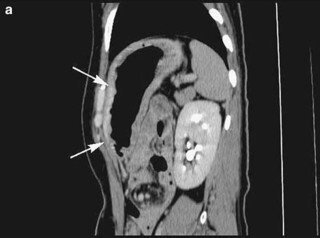

スキルス胃がん Ctの比較画像 進行をはじめてから7か月後

個別 スキルス胃癌のct診断は難しい 腹部ct の写真 画像 タカ派の画像診断医 写真館